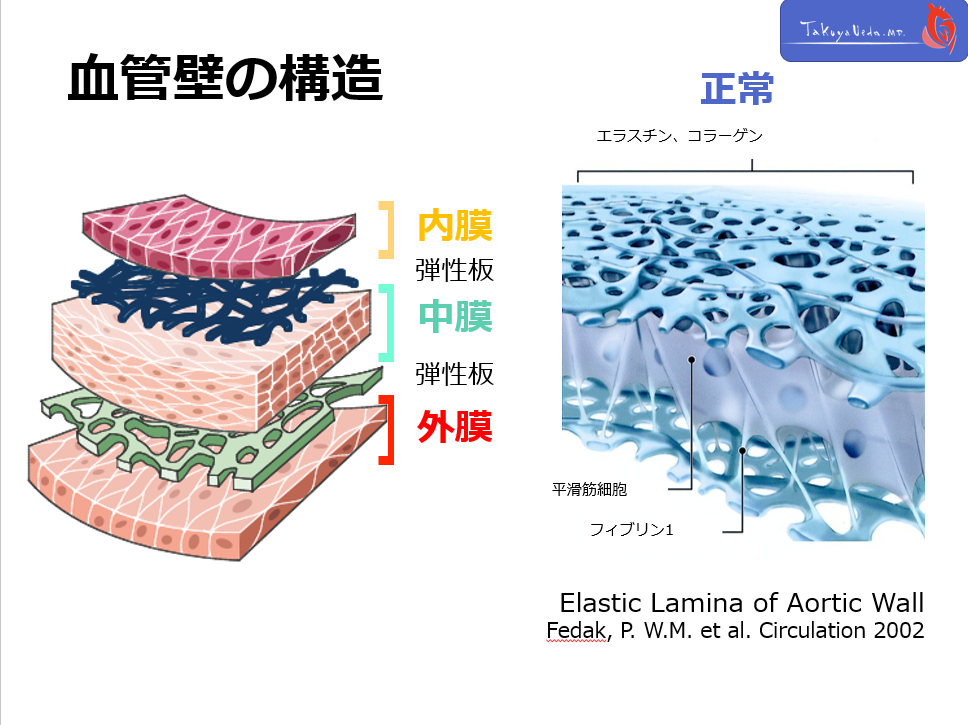

各病態の疾患概念を考える際に、大動脈の壁構造を理解することは非常に重要です。

大動脈壁は、Intima, Media, Adventitiaの3層構造よりなり、各層間をelastic laminaが区分しています。

CT上、これらの層構造自体を観察をすることはできませんが、どの構造に異常が存在するのかということを意識する事で、pathophysiology理解の助けとなります。

各病態の疾患概念を考える際に、大動脈の壁構造を理解することは非常に重要です。

大動脈壁は、Intima, Media, Adventitiaの3層構造よりなり、各層間をelastic laminaが区分しています。

CT上、これらの層構造自体を観察をすることはできませんが、どの構造に異常が存在するのかということを意識する事で、pathophysiology理解の助けとなります。

各病態の疾患概念を考える際に、大動脈の壁構造を理解することは非常に重要です。

大動脈壁は、Intima, Media, Adventitiaの3層構造よりなり、各層間をelastic laminaが区分しています。

CT上、これらの層構造自体を観察をすることはできませんが、どの構造に異常が存在するのかということを意識する事で、pathophysiology理解の助けとなります。